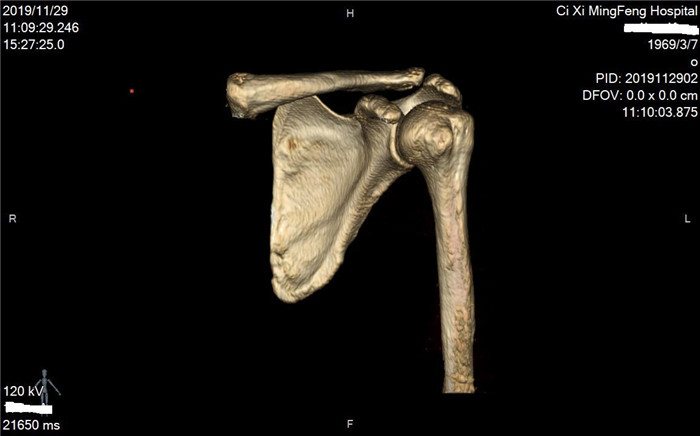

明峰CT搭載了領先的硬件技術平臺及系統,強大的掃描能力可滿足臨床的各種要求,呈現更極致的細節,為各臨床科室提供高品質的圖像。薄層掃描,消除部分容積效應,提高各向同性。配合高分辨率算法,有助于細微結構和形態學顯示。